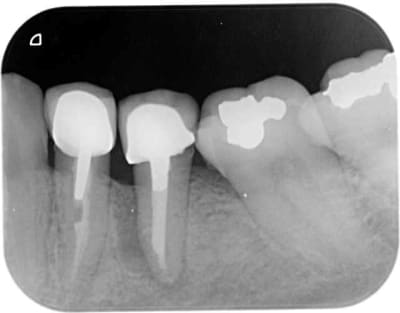

Olivier et les autres, pouvez-vous détailler ce qui dans le positionnement 3D a amené un tel échec esthétique?

Je dirai un axe vestibulo-palatin trop incliné en vestibulaire, mais est-ce la seule cause?

>Je dirai un axe vestibulo-palatin trop incliné en vestibulaire, mais est-ce la seule cause?<

est ce que c'est mieux pour l'axe?

un peu d'humour ne "nuit" pas

La patiente de mardi (74ans) "désaxée" est venue payée très contente et a amené un petit cadeau pour les assistantes

Comme le béotien se contente de peu il est content

Pxav la patiente de jeudi pas de douleurs pas de saignements

Ce n'est pas le première fois que j'utilise un implant comme bouchon (coût 80€). Mardi je décide si retourne tranquillement dans un mois, j'en mettrais bien 1 de plus en 34

Par contre la remarque de Noah m'a interpellé, je suis peut être par habitude devenu trop minimaliste, il faut savoir se remettre en cause

mardi pour la centrale je prend des photos du moignon tranvissé puis de la céram et on en discute

Pour arno et la patiente qui me vaut ces critiques, pour un autre axe il fallait simplement une greffe osseuse+ une gingivale et une expansion